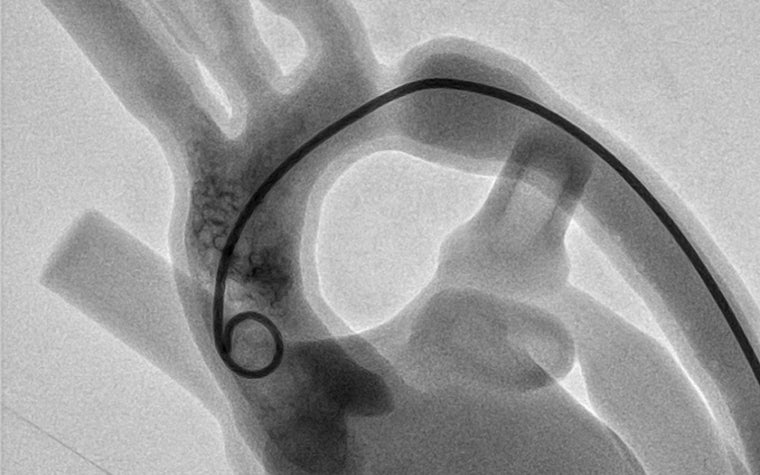

Effective medical training relies on the ability to perform practice treatments repeatedly. To enable particularly realistic catheter training for the interventional treatment of congenital heart defects the Department of Pediatric Cardiology at the Ludwig Maximilian University (LMU) Hospital in Munich came up with a novel solution. They developed 3D-printed models of children's hearts afflicted with heart defects. The latest generation of 3D-printed models can even beat like a real heart. The clinical team used Materialise's Mimics Innovation Suite software package to develop and modify the heart models.

The diagnosis and interventional treatment of congenital heart defects in children using catheter technology requires not only a detailed knowledge of the anatomy. It also requires analyzing potential problems, the necessary steps to correct them, and in particular, an enormous amount of dexterity when handling the catheter. The instrument must be guided extremely sensitively through the smallest spaces, and every intervention must be securely seated. However, there is no realistic training simulation set-up at this moment - neither for children's hearts nor for congenital heart defects. Unlike adult hearts, where there are at least virtual reality simulation systems for addressing typical adult diseases, education and training or the operation of children’s hearts still take place almost exclusively on humans.

Against this background, the idea of developing 3D-printed children's hearts specifically for training purposes was born at LMU Klinikum. Digital adaptations can be used to create a variety of models with different heart defects. Such replicas, adapted to the training objectives, offer physicians the opportunity to practice the treatment of typical clinical pictures as well as new instruments and procedures. Being able to do so repeatedly without risk, results in an enormous boost in confidence. Since the training models can be used multiple times and a new patient scan is not necessary for every heart defect, they have a long-term cost advantage over patient-specific representations. At the same time, they save young patients from unnecessary exposure to radiation and sedation, as no patient scans are required to produce new models using the digital modeling method.

"Feedback from the workshops held so far for students, residents, and experienced pediatric cardiologists using the 3D-printed heart models has been overwhelmingly positive," said Prof. Dr. Haas. "Among other things, the experienced players emphasize the realistic character of the replicas, including the haptic and anatomical replication as well as the procedural simulation of the interventions. I can confirm this positive finding. Entire intervention teams can gain confidence in this catheter application under realistic conditions."

University Prof. Dr. Ina Michel-Behnke from the Pediatric Heart Center Vienna substantiates the benefits: "We trained our students and postgraduates who are not regularly involved in interventions on-site in the cath labs, using the 3D heart models, and could see a rapid improvement in handling skills, as well as a reduction in the duration of the procedure and radiation. The trainee pediatric cardiologists felt much more comfortable with their first patient cases after being introduced to them through this module of interventional training and were very relieved to be able to keep the radiation dose to their patients low."

Prof. Dr. Haas believes the new heart models are groundbreaking: "Because of the numerous benefits associated with such 3D-printed models, I believe that training on them should be an integral part of pediatric cardiology training. Training on them can be carried out regularly in any hospital equipped with a cardiac catheterization laboratory without a major financial and technological outlay. As a result, hand movements and processes are internalized faster and better."